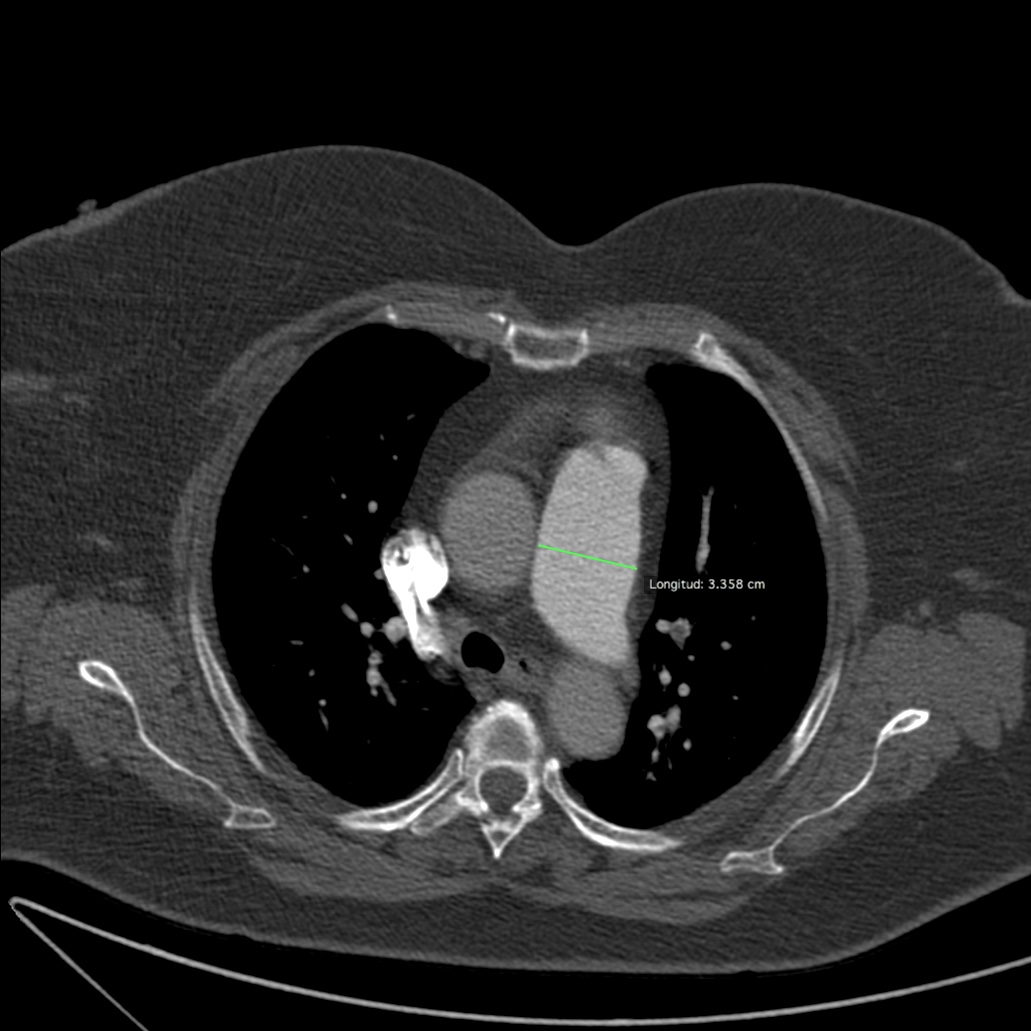

Signo de Rail de tren en un corte perpendicular a la arteria segmentaria del LM, sugestivo de TEP agudo.